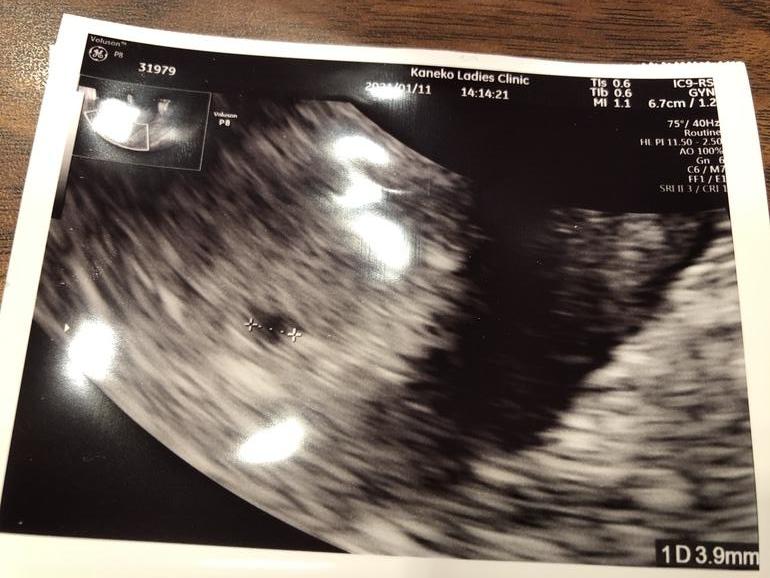

Вчера была на узи . Малыш подрос со среды до понедельника на 5 мм( не знаю , хорошо это или плохо) , сердцебиение есть. Врач сказал , что пока все хорошо , но будут наблюдать( из-за предыдущей зб и выкидыша ), дали телефон для консультаций на всякий случай.По данным врача похудела на 6 кг с начала беременности( на домашних весах как-то меньше по

Сходила сегодня на узи, за неделю плодное яйцо выросло практически в 5 раз и составляет практически 15 мм, было 3 мм неделю неделю назад , желточный мешочек есть, а эмбриона не видно . Сходили придти на повторное узи через неделю . Я верю в своего малыша и в то, что на все Воля Божья. ( и мне кажется , что внутри плодного яйца все-таки что -то